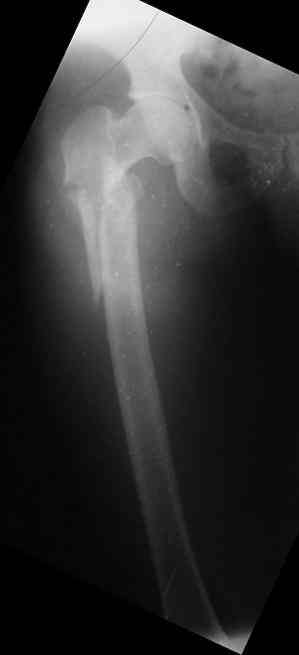

Male, 75 yrs old.

Right hip fracture as an interthrocanteric with extension to diaphysis Tronzo V.

Option for treatment:

1. DHS

2. 90 - 95 g AO Plate (Condylar Plate)_

3. Reconstruction Hip Nail

4. Intertrochanteric Nail System

5. Externa hip fixator

Every listed option is acceptable in general. Least invasive and most stable to allow immediate unprotected weight-bearing will be closed nailing, better using a recon nail with trochanteric insertion. I am not sure what you mean as "Intertrochanteric Nail System" but Gamma or other nails of proximal type with 15-17 mm diameter of the proximal part seem to be too large for 15 y.o.

My answer for this case - Prosimal femoral nail

Targon (Aesculap)